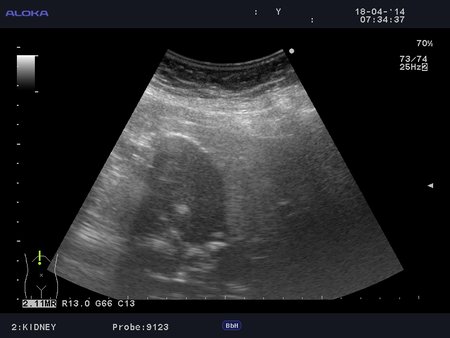

Еще случай.

Бабушка из отделения сестринского ухода, без жалоб на боли в животе. Лаб. анализы не изменены.

Если кальциноз стенки полный и содержимое пузыря осмотру не доступно, то есть показания к проведению КТ-МРТ. Если стенки инкрустированы частично (как в представленных случаях) и можно оценить характер содержимого и структуру стенок, то можно ограничиться только УЗИ. Далее, если есть подозрение на опухоль то пациента направляют к онкологу, а он сам определяет дальнейшую тактику.